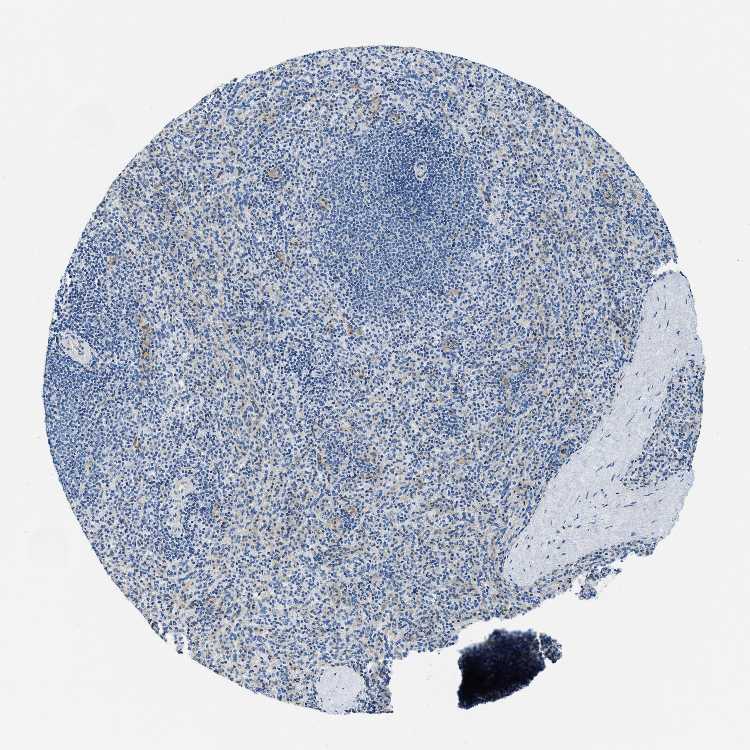

SPLEEN - Antibody stainingi

Antibody staining in the annotated cell types in the current human tissue is reported as not detected, low, medium, or high, based on conventional immunohistochemistry profiling in selected tissues. This score is based on the combination of the staining intensity and fraction of stained cells.

Each image is clickable and will lead to virtual microscopy that enables deeper exploration of all samples and also displays staining intensity scores, fraction scores and subcellular localization as well as patient and tissue information for each sample.

Antibody HPA018116

Cells in red pulp Not detected

Cells in white pulp Not detected